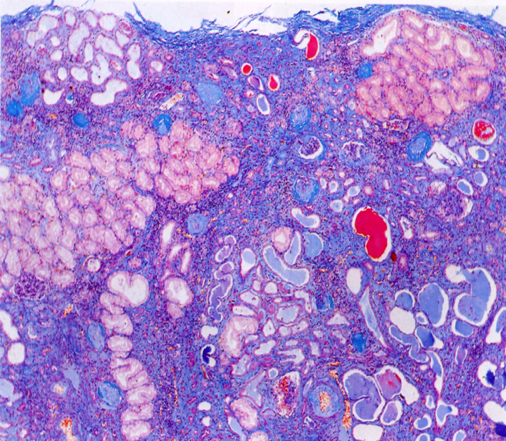

大体:两侧肾脏对称性固缩,表面呈微小颗粒状,故称之为颗粒性固缩肾(granular nephrosclerosis)。切面观,皮质变薄,皮髓质分界不清。

光镜下:大量肾小球硬化、玻璃样变(超过全部肾小球的50%)。肾小球中央部分变为无细胞、嗜伊红、PAS阳性之玻璃样小体,周围部分纤维化(如下图)。少数肾小球结构残存。硬化肾小球所属肾小管萎缩、消失、使玻璃样变的肾小球相互靠拢集中。残留肾单位常呈代偿性肥大,肾小球体积增大,肾小管扩张。间质纤维组织增生并有大量淋巴细胞、浆细胞浸润。间质内小动脉硬化,管壁增厚,管腔狭窄。

(肾小球纤维化及玻璃样变,所属肾小管萎缩、消失。间质纤维化伴炎细胞浸润。)

(纤维被染成了蓝色)